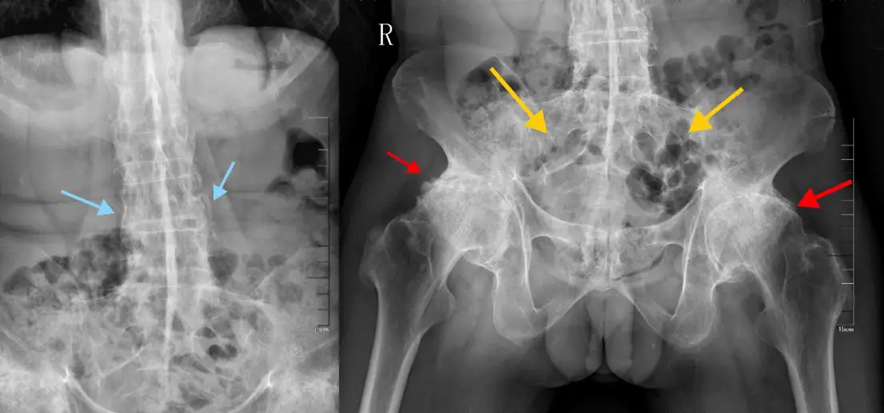

“Bệnh thường tấn công các khớp ở cột sống, khớp cùng - chậu, và hông. Khi tiến triển nặng, cột sống có thể dính cứng như một cây tre, khiến người bệnh không thể cúi, ngửa hay xoay lưng”, bác sĩ Vạn cho biết.

Cột sống của bệnh nhân bị viêm cột sống dính khớp có những thay đổi "giống như cây tre"